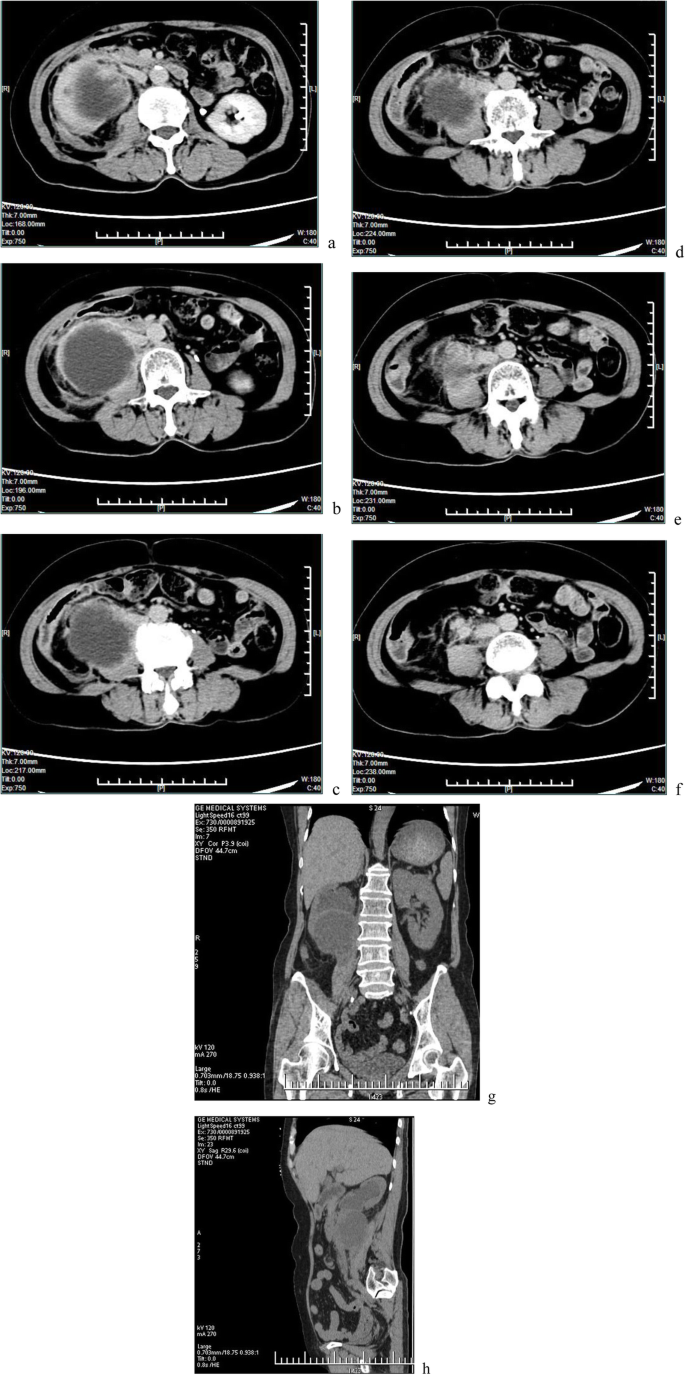

Her chest X-ray was within the normal range, but ultrasonography of the urinary system revealed heavy hydronephrosis of the right kidney. Contrast-enhanced computed tomography (CECT) of the abdomen showed marked hydronephrosis of the right kidney (which presented as a cyst-like structure), and some perinephric exudates (Fig. 1a-c). Further CECT (Fig. 1d-f) and CT (coronal and sagittal, Fig. 1g,h) of the abdomen revealed right gross hydronephrosis with a markedly dilated cystic pelvicalyceal system and right perinephric chronic inflammation; a tumor could not be completely ruled out in the lower pole of the right kidney due to uneven renal parenchyma and mild to moderate enhancement in the nephritic phase. Renal radionuclide imaging revealed that the glomerular filtration rate (GFR) of the right kidney was 12.3 mL/min, GFR of the left kidney was 57.9 mL/min and the total GFR was 70.2 mL/min (normal GFR>64.8 mL/min). A careful study of the imaging ruled out the presence of any other systemic involvement. Infectious lesions were considered before surgery, but tumors could not be excluded. The patients and her family members refused to perform other further examinations.

a-c Contrast-enhanced computed tomography showed marked hydronephrosis of the right kidney and some perinephric exudates. d-f. Contrast-enhanced computed tomography revealed right gross hydronephrosis and right perinephric chronic inflammation; in the lower pole of the right kidney, a tumor could not be completely excluded with mild to moderate enhancement. g,h Plain scan of coronal and sagittal images

Ultrasonography typically only reveals only hydronephrosis. Conversely, CT is an important tool and can provide high-resolution imaging to evaluate masses and stages in renal malignancies. In the present case, CECT revealed hydronephrosis with a markedly dilated cystic pelvicalyceal system with perinephric chronic inflammation. This is consistent with the renal specimen seen after resection. Ureteral obstruction is the main cause of the presenting symptoms.